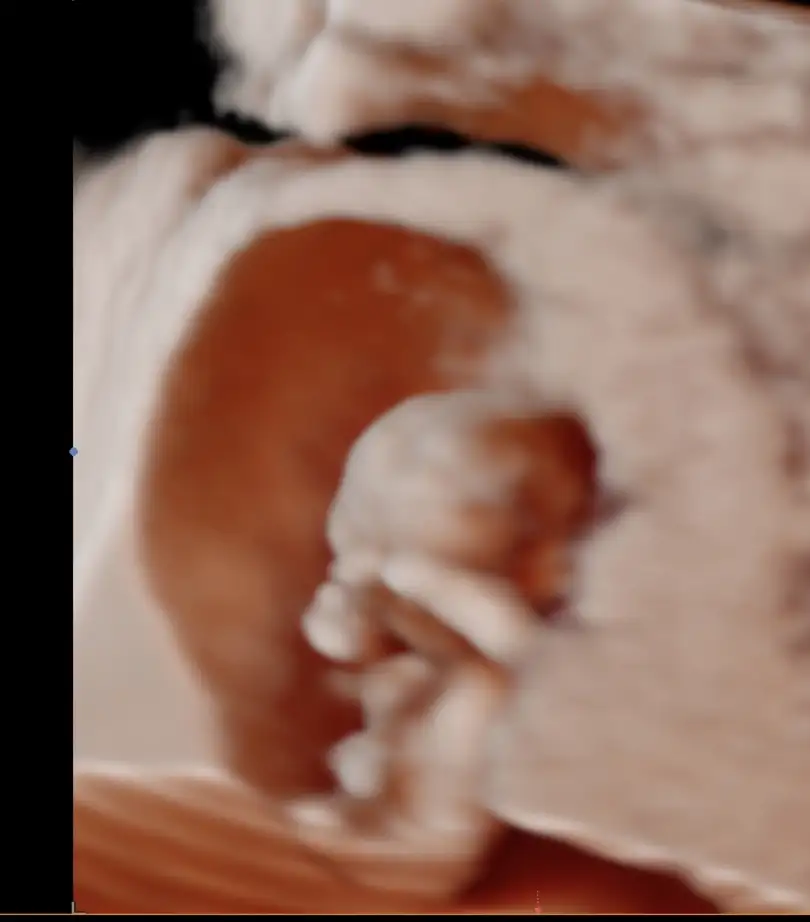

11+5 tahmini alabilir miyim:)